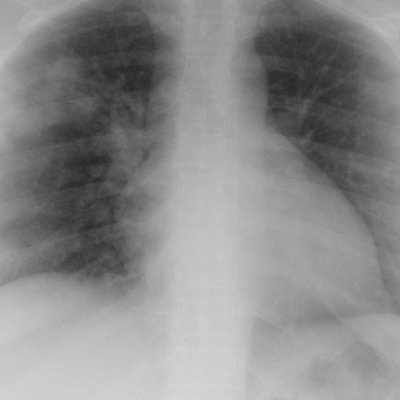

Фото: commons.wikimedia.org/Hellerhoff (Creative Commons Attribution-Share Alike 3.0 Unported license)